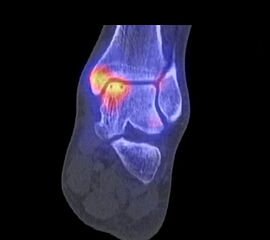

Die Kombination von SPECT und CT in einem Untersuchungsgang bringt wie bereits oben erwähnt eine erhöhte Ortsauflösung und artefaktfreie Darstellung von Knochenstoffwechselveränderungen der SPECT bei gleichzeitig excellent guter anatomischer Darstellung/Zuordnung durch die CT 3. Auf die Vorteile der CT gegenüber dem konventionellen Röntgen muss nicht mehr besonders eingegangen werden. Besonders eignet sich die „SPECT-CT“ zur Diagnostik von Fußerkrankungen (Biersack HJ et al. 2012).

Aufgrund der optimalen funktionellen Darstellung (PET) und der entsprechend guten anatomischen Bildgebung kann dieses kombinierte Untersuchungsverfahren viele Fragestellungen auch im Bereich des Fußes beantworten. Exemplarisch werden folgende Indikationen erwähnt. Abklärung von Infektionen im muskuloskelettalen Bereich 45, Untersuchungen von unklaren Fußschmerzen (Biersack HJ et al. 2012), präoperative Bildgebung beim Charcot-Fuß/diabetischer Fuß 31.